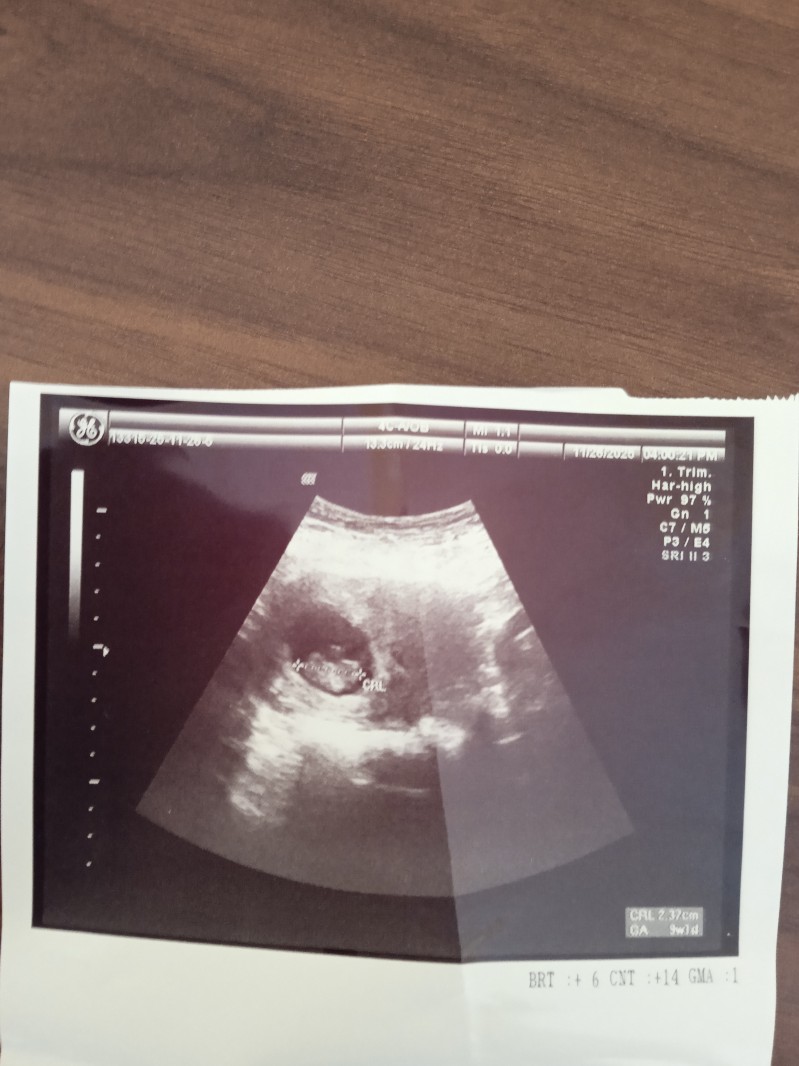

Cinsiyet tahmini

Kiz bence kese yuvarlanma kiz oluyor

Karından mı cekıldı vajınadan mı normalde doğruluk payı yok canm ama keseye göre tahmınde bulunacam

Erkek o zaman canm Tabı ne kadar doğru olur bılemem

Canm bebek sağdaysa erkek soldaysa kız derler ultrasonda sagda olan solda solda olan sağda görünür sizin bebek saga yerlesmıs Tabı ultrasonda solda gorunmus

Ben daha önce bu resime yine kız demiştim kese yuvarlak hakkiniza hayırlısı

Keseye göre kız gibi canım benim kesemde böyle kızım olcak yeni öğrendim